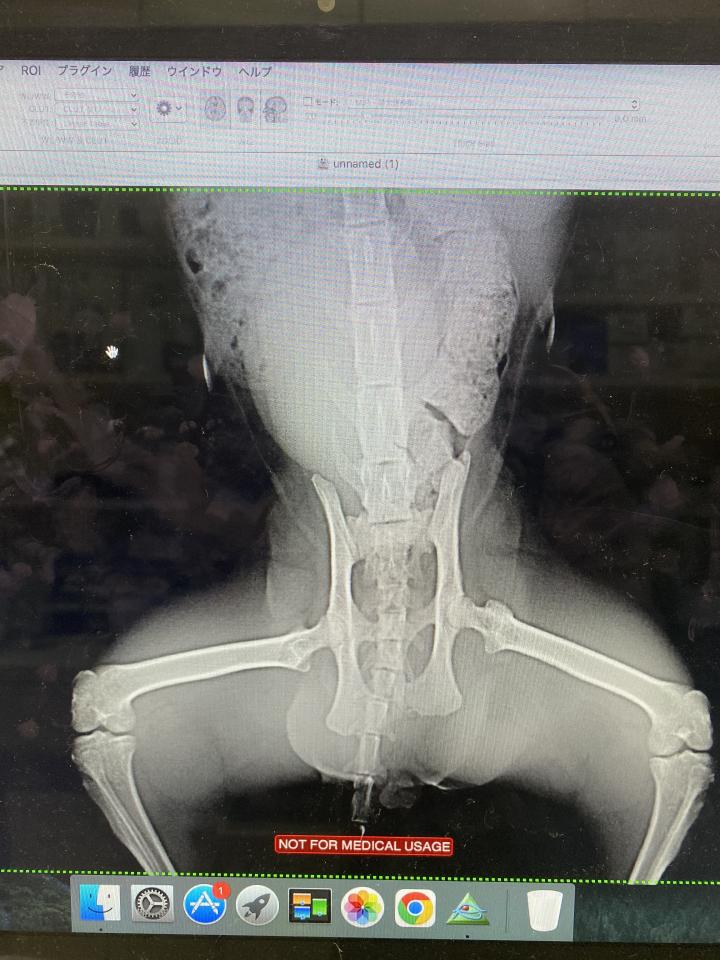

諸々の検査をしてもらうと、結果は骨盤骨折

治療の第一選択は整復手術

ですが、それには手術だけで40万円という高額な治療費がかる

自然治癒でそのまま骨は着きますが

今後、歩行障害や骨盤が狭くなる事による排泄障害が出てくる可能性もあるとのこと